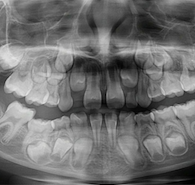

Na imagem abaixo é possível ver a foto oclusal inferior de uma menina de 6 anos de idade com fusão dos dentes 72 e 73, 82 e 83 e agenesia dos dentes 32 e 42.